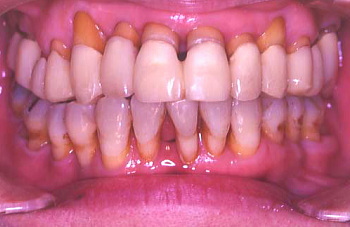

① 初診時の口腔内の状態:歯と歯の間に黒い歯石が見られ、歯肉は腫れている。

② 患者の熱心な歯磨きと医師や衛生士の機械的な歯のクリーニング(PMTC)により、 歯肉は艶を取り戻した。